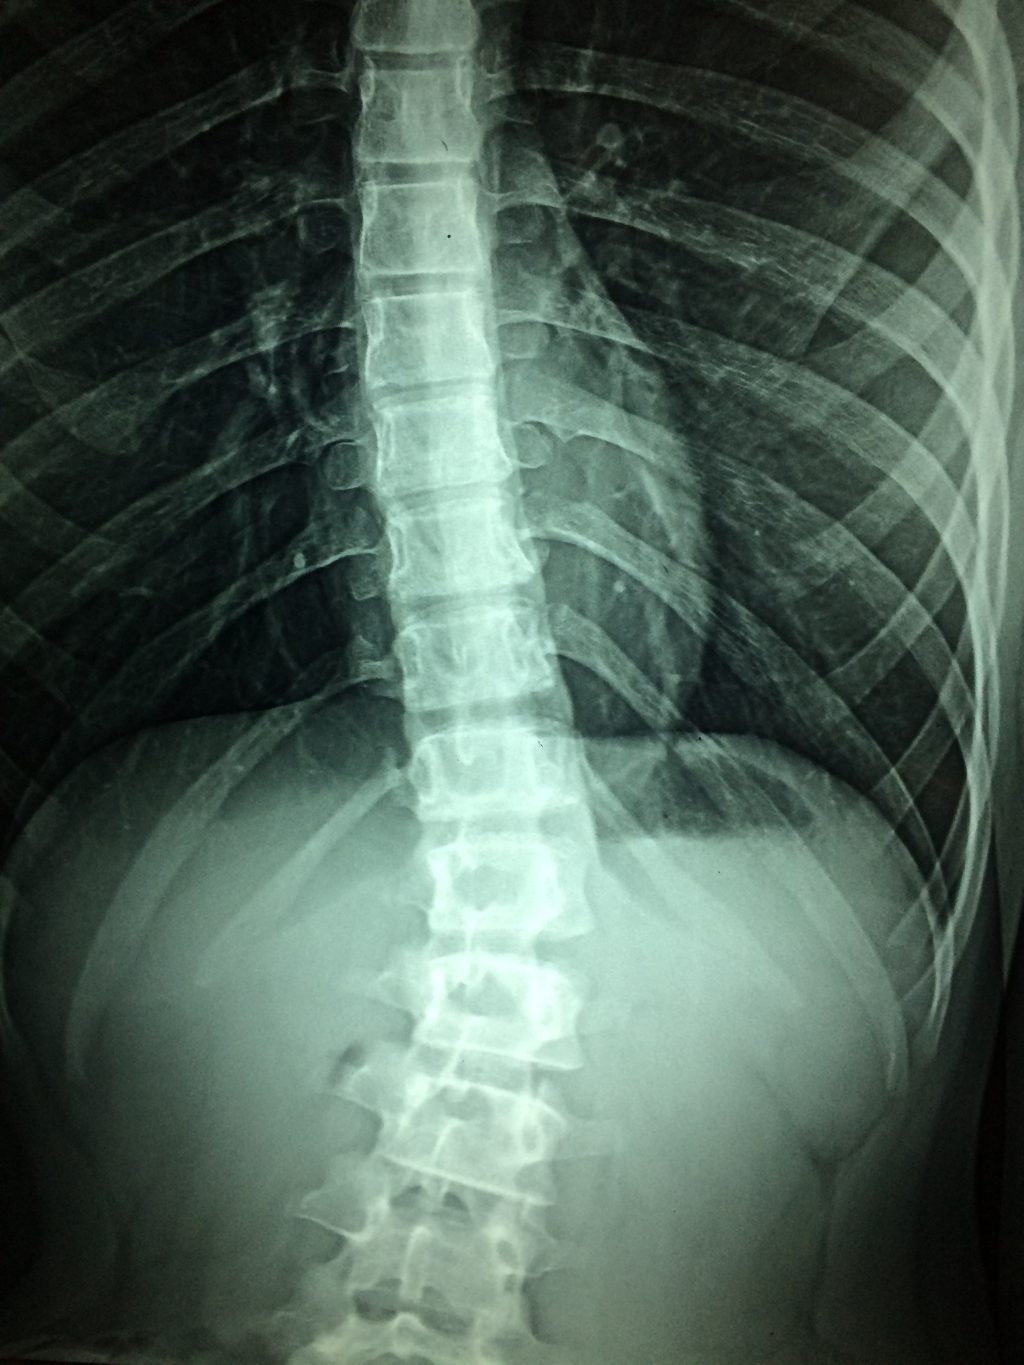

Segundo os estudos realizados, até o presente momento, é possível concluir que o medicamento deve demonstrar tanto eficácia quanto segurança para utilização em pacientes na fase aguda, com um período de aplicação de até 72 horas após a lesão. Os participantes do estudo devem ter entre 18 e 72 anos e apresentar lesões completas na medula espinhal torácica, situadas entre as vértebras T2 e T10, com indicação para cirurgia.